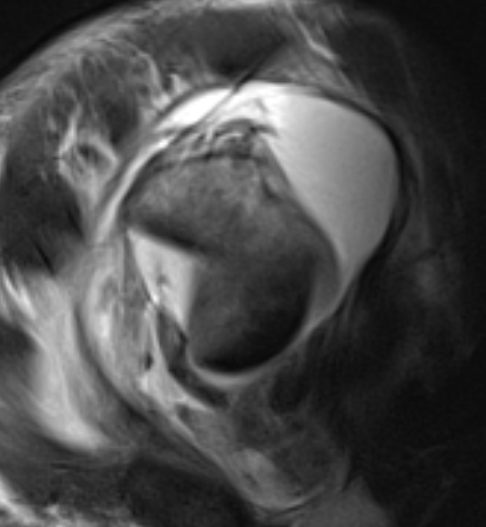

MRI

Rotator cuff tears

MRI with massive supraspinatus tear, subscapularis tear, and large Hill Sachs lesion